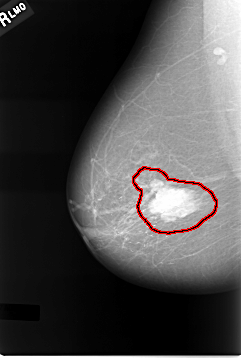

C_0011_1.RIGHT_MLO

RIGHT_MLO LINES 5720 PIXELS_PER_LINE 3848 BITS_PER_PIXEL 12 RESOLUTION 50 OVERLAY

FILE: C_0011_1.RIGHT_MLO.OVERLAY

TOTAL_ABNORMALITIES 1

ABNORMALITY 1

LESION_TYPE MASS SHAPE LOBULATED MARGINS CIRCUMSCRIBED

ASSESSMENT 5

SUBTLETY 5

PATHOLOGY MALIGNANT

TOTAL_OUTLINES 1

BOUNDARY